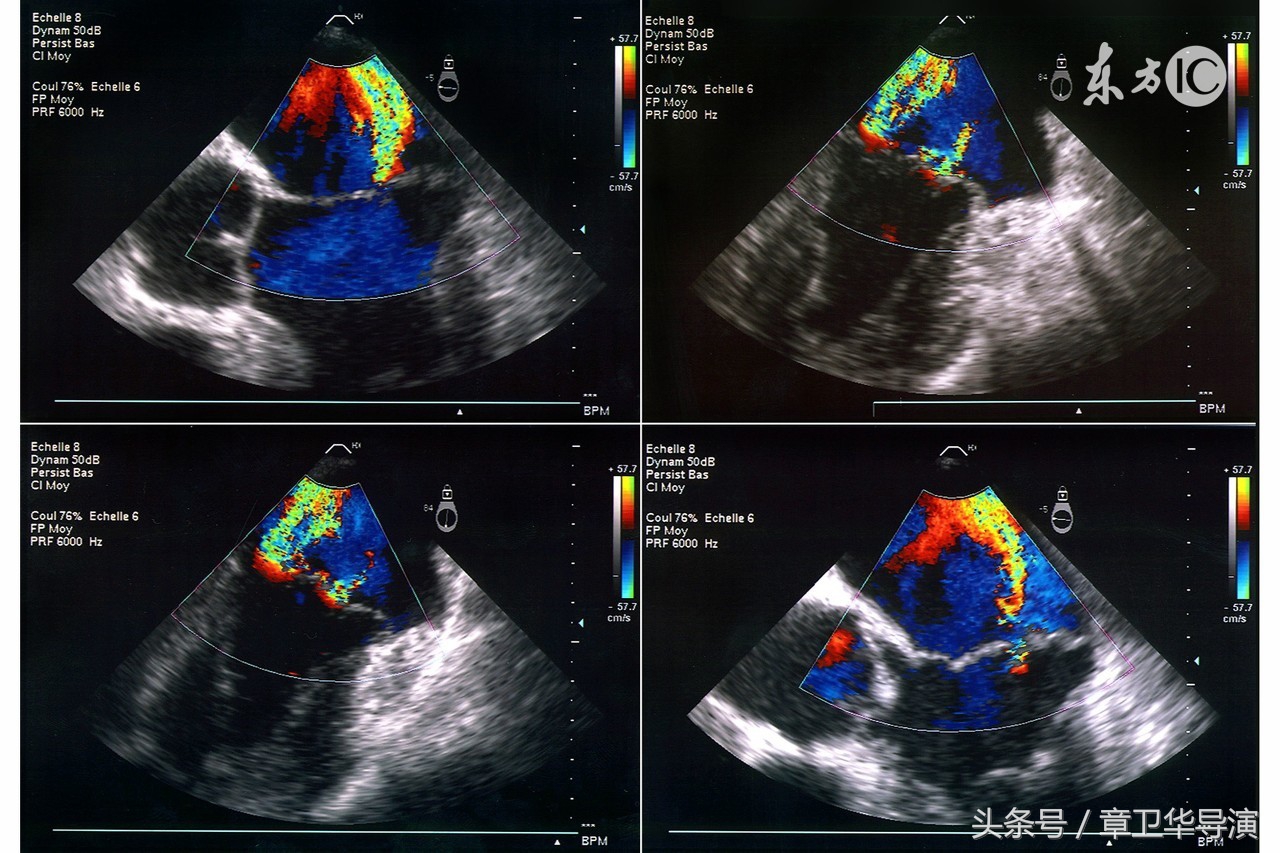

7、什么是多普勒超声?

这个检查是在怀孕阶段通过经腹超声完成的。声波用于计算胎儿脐带或者其他血管中的血流,也用于监测胎心。